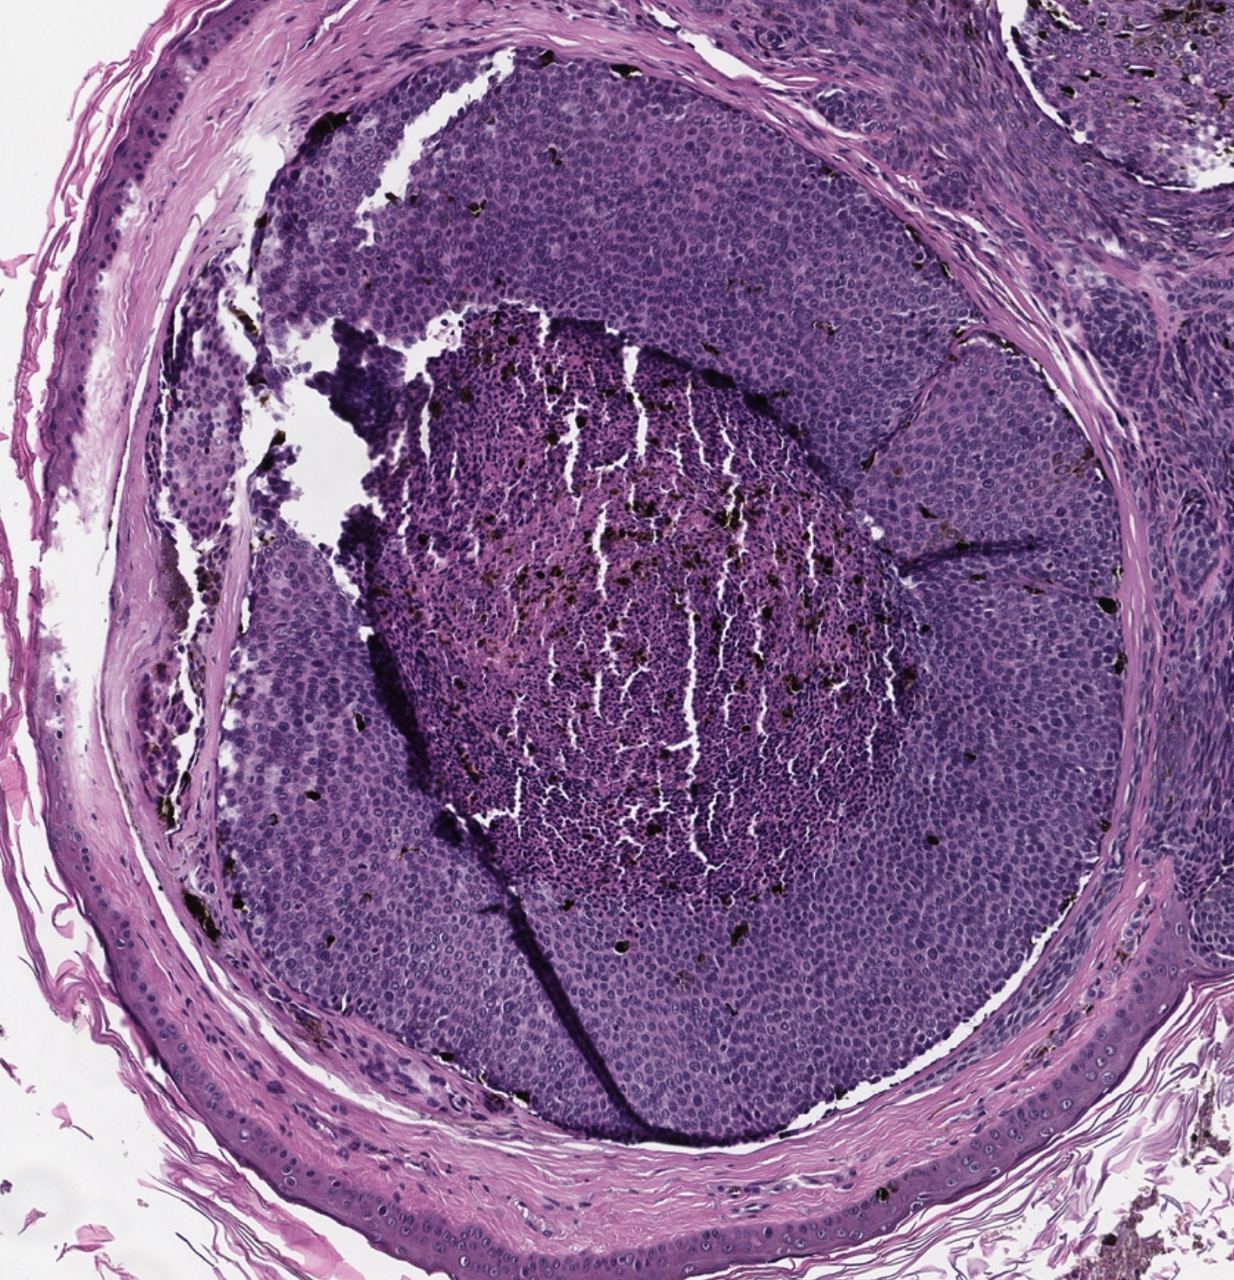

Базально - клеточная опухоль